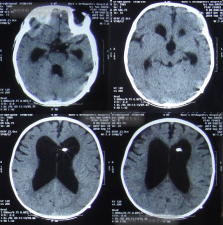

但出院后2天即2018年7月26日,晨起患儿双眼出现对眼,喂奶后再次喷射性呕吐,就诊于第2家医院:吉林省珲春市某医院,检查后认为患儿较重建议转院,于是当天就诊于上级的第3家医院:吉林省延边市某三甲医院,查头颅CT示脑积水(图-1)。

图-1:2018年7月26日头颅CT